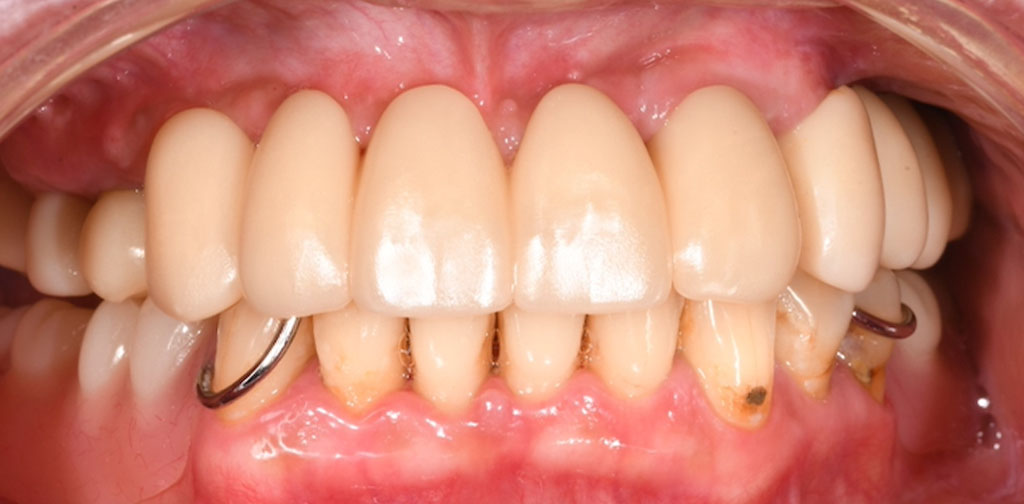

After1

インプラントと骨がしっかり結合するまで3ヶ月待ち、インプラントの上に人工の歯を被せる治療を行いました。